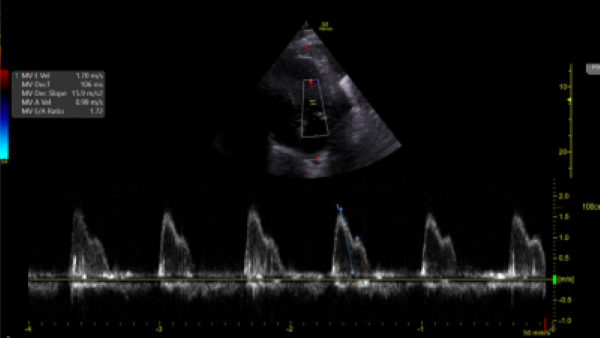

Image 2. Pulsed-Wave Doppler of mitral inflow pattern reveals mitral E velocity 1.70 m/s and E/A 1.72.

To measure diastolic dysfunction, start by obtaining an apical four chamber, place pulse-wave doppler over the tips of the mitral valve leaflets, and transmitral velocity times can be measured (Image 2). Peak E wave velocity correlates with early diastolic filling rate, mitral annular e’ velocity reflects LV relaxation rate (Image 3), and both values are used to calculate E/e’ which correlates with left ventricular filling pressures.

This patient has risk factors for diastolic dysfunction, such as left systolic dysfunction and regional wall abnormalities. His E/A is above the cutoff of 0.8 (E/A 1.72), which is characteristic of normal or pseudonormal inflow pattern. The E/e’ is low, classified as having grade 2 diastolic dysfunction, and implicating that the mean LA pressure is elevated.